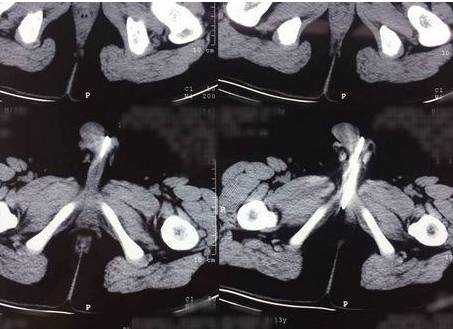

了解情况后,医生安排皮皮做了X光检查。检查结果让医生大吃一惊——皮皮的体内有20多颗珠子一样的异物吸附在一起,其中十几颗进入了膀胱,另外有几颗卡在尿道口。随后,皮皮被转到温医大附二院小儿外科进一步治疗。

小儿外科医生王永飚说,他先是想伸入尿道镜夹出珠子,但尿道口太小,珠子又排成了两个一组的“队伍”,加上珠子有很强的磁性,镊子一进去就会被吸住。情况有些棘手,医生决定给皮皮做膀胱切开异物取出术,手术进行了2小时左右。

王永飚介绍,切开膀胱后,他看见里面有10多颗磁珠,另外有七八颗珠子牢牢地卡在皮皮的后尿道处。一般11岁孩子的尿道直径在5毫米左右,而珠子直径为3毫米,进入体内之后两个一组吸在一起,也就是说6毫米的异物卡在了尿道处,引起了尿道的肿痛、流血。最终,医生共取出了26颗。